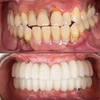

Zirkonyum uygulamalar

Porselen uygulamaları

Laminate veneer